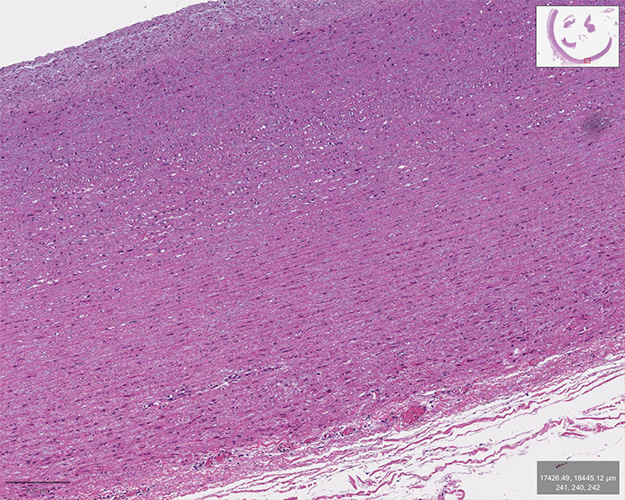

Immunofluorescent Imaging and Spatial Transcriptomics of Coronary Arteries

These images showcase cross-sections of human coronary arteries stained with fluorescently labeled antibodies. CD68 (red) marks macrophages, while DAPI (blue) labels cell nuclei. The samples compare coronary plaques from people living with HIV (PLWH) and people without HIV (PWoH), highlighting differences in immune cell infiltration across early and late stages of atherosclerosis.

Outlined regions represent manually selected regions of interest (ROIs) for downstream spatial transcriptomic profiling using the NanoString GeoMx Digital Spatial Profiler. These ROIs were selected based on immune marker expression and plaque morphology to capture spatially resolved gene expression data from distinct microenvironments within the lesion, enabling insight into how HIV status may influence the local immune landscape and atherosclerotic progression.